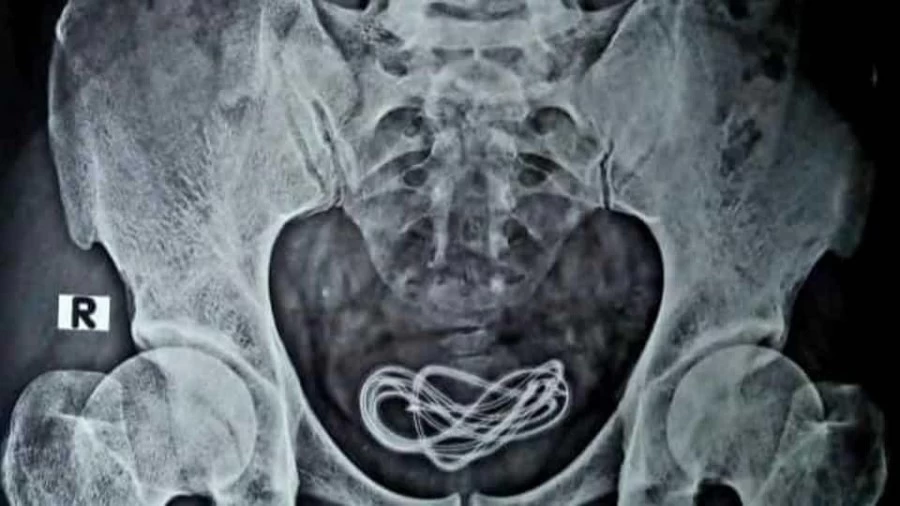

The 30-year-old man approached the doctors in the Assam hospital after five days of inserting the cable but repeatedly told them that he had consumed it. He was operated upon after his stool was examined and an endoscopy was conducted on him but when nothing was found in his gastrointestinal tract, Islam decided to take his X-ray. The reports showed a mobile charging cable lying inside his urinary bladder.

Taking to his Facebook handle after removing the cable wire subsequently, Islam shared his amusement by posting a video of the surgery along with pictures of the X-ray and the retrieved wire. He captioned it, “Surprises in Surgery! After 25 years of experience in Surgery, I continue to be surprised and shocked by instances like this where my intellectual and surgical skills are challenged….a 30 year old man came to me with complaints of pain abdomen and history of accidental ingestion of headphones . I operated upon him to find nothing in his Gastrointestinal tract…but instead discovered a mobile phone charger cord in his Urinary Bladder ….all of you must have guessed the entry point and route ( it entered through his penile urethra to his urinary bladder)…his mental health remains a question….surgery was successful and the patient is recovering….everything is possible on this earth, indeed! (sic).”